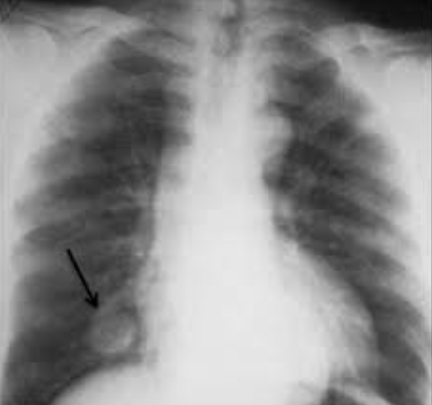

고립성 폐결절은 다양한 원인에 의해 발생할 수 있으며, 이 중 하나는 폐암입니다. 결절의 크기, 모양, 가장자리의 성질, 성장 속도, 그리고 환자의 병력 등에 따라 결절이 암일 가능성을 추정할 수 있습니다.

결절의 크기는 암의 가능성과 큰 연관이 있습니다. 일반적으로 8mm 미만의 결절은 암의 위험이 상대적으로 낮지만, 결절이 커질수록 암일 가능성이 증가합니다. 그러나 크기만으로는 암을 확정할 수 없으며, 다른 속성들도 함께 고려해야 합니다.

예를 들어, 결절의 모양과 가장자리의 성질도 중요한 특징입니다. 부드럽고 둥근 결절은 암의 위험이 더 낮은 편이지만, 모서리가 날카롭거나 불규칙하거나, 속이 공동으로 되어 있는 "스펀지 같은" 결절은 암일 가능성이 더 높습니다.